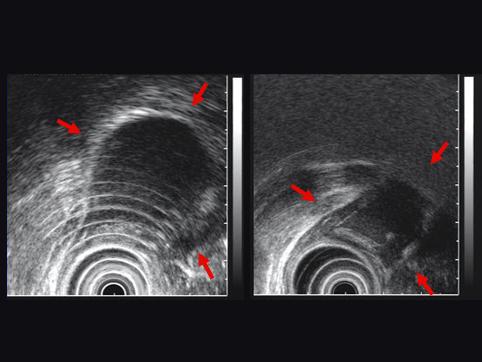

症例提示(所在地,施設名等): 佐賀県・ 佐賀大学医学部放射線科 (水口先生からの提供症例)

疾患(病理主体)の分類良性非上皮性腫瘍/嚢胞

部位(臓器別)食道/下

検査方法エコー

病変の最大径(ミリ)40以上